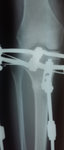

Дата операции 05.04.2016г.

Дата снятия аппаратов 05.07.2016г.

Срок лечения 90 дней.